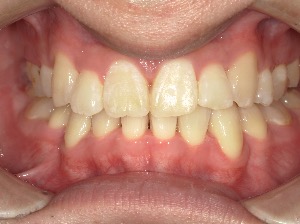

before

after

患者さんの年齢 20代 女性 症状 ガタガタを治したい 治療内容 マウスピース矯正治療 費用 90万(税抜) 治療期間・回数 治療期間2年、通院回数10回 メリット 笑顔が綺麗 デメリット・リスク 期間がかかることがある - マウスピース矯正